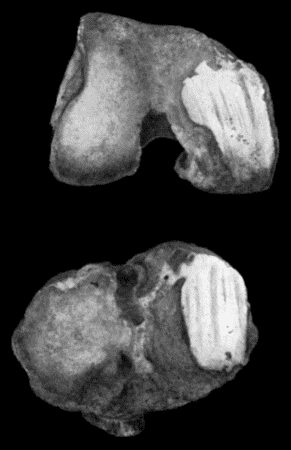

162.Bones of Knee in Charcot's Disease 533

163.Charcot's Disease of Left Knee 534